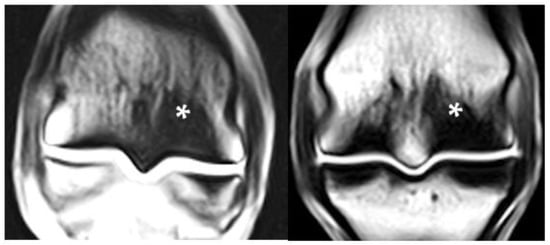

3.7. Combinations of PSG Pathology

3.8. Fetlocks with Possible Fracture Pathology